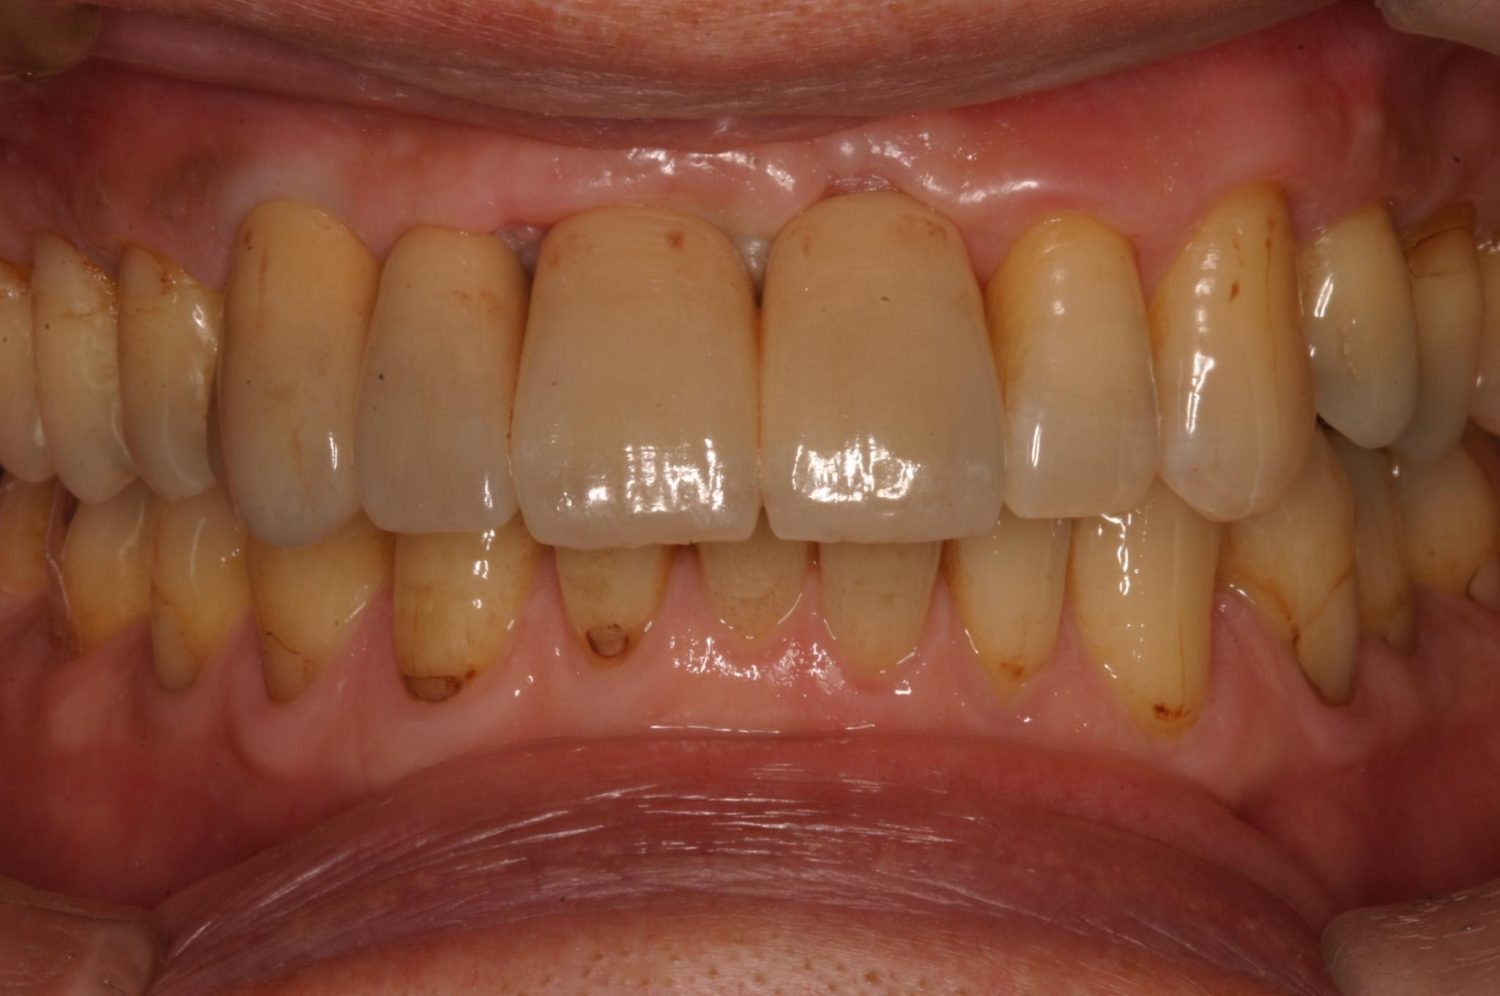

Before

After

前歯部審美ゾーンの骨造成術及びインプラント症例。